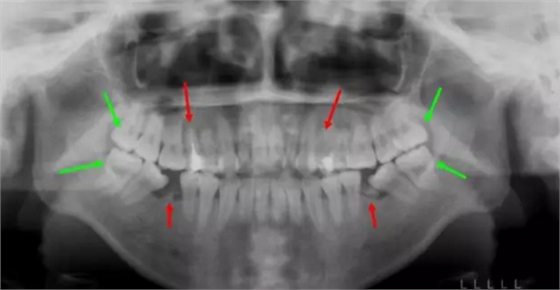

這個(gè)妹子正畸前,前牙不能咬合,牙凸又嘴凸而且還有殘余的牙根,牙列開始傾斜。綜合考慮后,醫(yī)生拔除了箭頭所示8顆牙,沒有采取常規(guī)拔牙,因?yàn)樾枰M量拔除不能保留的病牙。

矯正結(jié)束后,姑娘收獲了整齊的牙齒和完美的微笑~